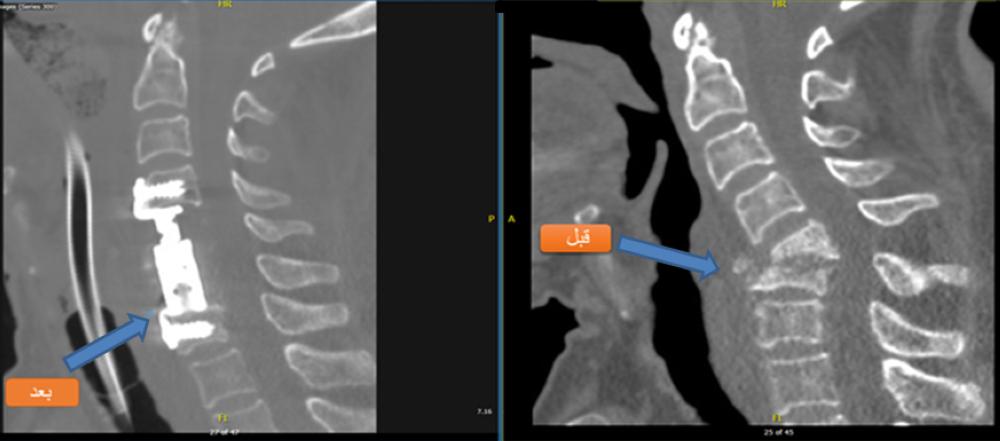

وقد دخل المريض المركز الطبي بينبع الصناعية للعلاج من مرض بكتيريا الدرن، والتي كانت تتمركز بالعمود الفقري العنقي، والتي تسببت في تفتت وانخفاس الفقرتين 5 و6 مع انحراف العمود الفقري العنقي، والذي أدى إلى الضغط الشديد على النخاع الشوكي، بعد ذلك قرر فريق الجراحة بالمركز الطبي بقيادة استشاري جراحة المخ والأعصاب والعمود الفقري الدكتور نبيه بن عبدالرحمن باجنيد، التدخل الجراحي بواسطة الميكروسكوب العصبي بإزالة الفقرتين المصابتين بالكامل، واستبدالهما بالمباعد المصنوع من مادة التيتانيوم، وإعادة العمود الفقري إلى وضعه الفيزيائي الصحيح، وتحرير النخاع الشوكي تماما.